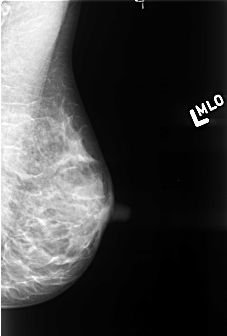

B_3422_1.LEFT_MLO

LEFT_MLO LINES 4360 PIXELS_PER_LINE 2944 BITS_PER_PIXEL 12 RESOLUTION 50 NON_OVERLAY